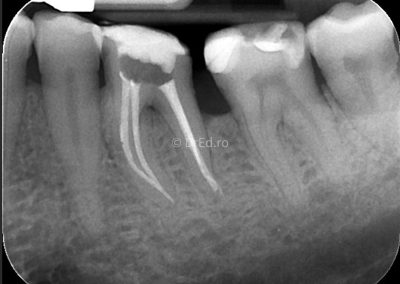

Galerie

Toate imaginile, fotografiile și radiografiile publicate pe acest site sunt protejate prin drepturi de autor și constituie proprietatea exclusivă a Dred.ro.

Aceste materiale sunt furnizate exclusiv în scop informativ și educațional și nu conțin date cu caracter personal sau informații care permit identificarea pacienților, în concordanță cu legislația privind protecția datelor cu caracter personal și GDPR.

Reproducerea, copierea, distribuirea, publicarea, transmiterea, modificarea sau orice altă utilizare, integrală ori parțială, a acestor materiale, în orice formă și prin orice mijloace, fără consimțământul prealabil scris al titularului drepturilor, este strict interzisă și poate atrage răspunderea civilă și/sau penală, în condițiile legii aplicabile privind drepturile de autor și protecția proprietății intelectuale.